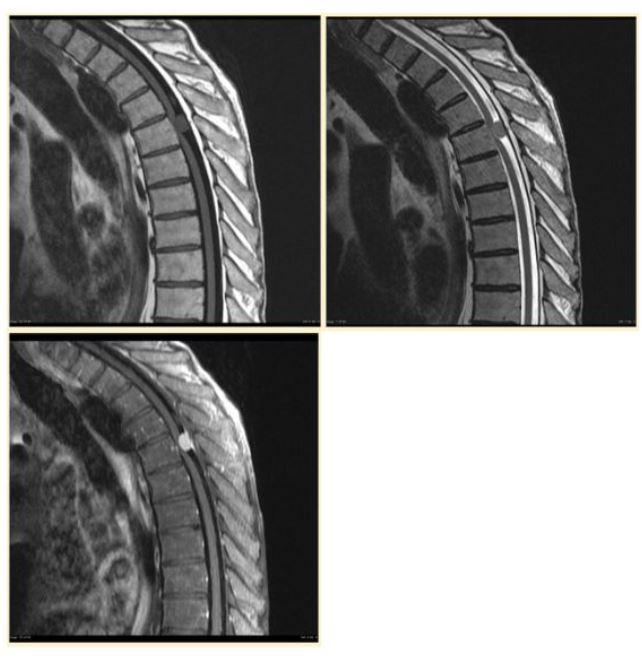

A spinal MRI shows bright cerebrospinal fluid surrounding the cord. Which sequence is most likely being viewed?

A. T1

B. T2

C. Diffusion-weighted

D. Gradient echo

139

A radiologist wants to look for edema around a spinal cord lesion. Which sequence is generally most useful?

C. Plain radiograph

D. CT bone windows

140

A lesion becomes more conspicuous after gadolinium administration. This is typically assessed on:

A. T1 post-contrast

B. T2 without contrast

C. Noncontrast CT

D. Ultrasound Doppler

141

card image

T1

T2

T1 with contrast